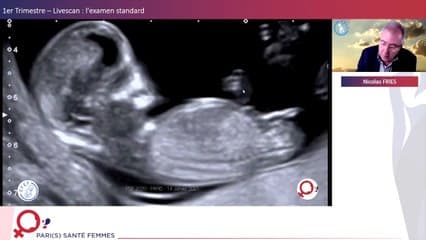

La plus grande ressource vidéo en échographie fœtale de France. Conférences, cours magistraux, démonstrations pratiques et podcasts par les experts du Collège Français d'Échographie Fœtale.

Vous y trouverez des conférences présentées lors des congrès nationaux et internationaux, des cours magistraux dispensés par des experts reconnus, des démonstrations pratiques sur des cas cliniques réels, ainsi que des podcasts et tables rondes sur les dernières avancées de la spécialité.